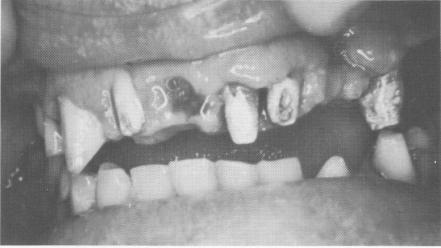

Fig. 15-40. The maxillary anterior quadrants of teeth were prepared at the expense of their labial surfaces to bring in the final tooth restorations. Root canal therapy was completed by filling the canals from the labial surfaces. The two posterior quadrants in the mandible were also prepared for full crown restorations.

3 Upper anterior teeth, lower posterior teeth prepared for restorations